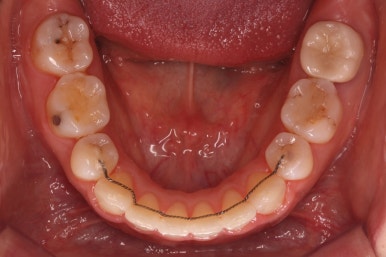

아랫니 모습입니다.

남아있는 발치의 공간이 없어졌으며 큰 이동이 없이 마무리가 되었습니다. 안쪽에는 발치공간이 다시 벌어지지 않도록 유지철사를 길게 연장해서 붙였습니다.

아래쪽의 앞니에는 잇몸뼈가 없기에 자칫 뿌리가 다 드러날 수 있는 위험한 상태였습니다.

다행히도 잇몸이 덮고 있었고 조심스레 마무리를 했기 때문에 추가적인 악화는 없었습니다. 그래도 아래앞니 쪽은 잇몸뼈가 약하기 때문에 평생 조심을 해야 한다며 거듭 말씀드리고 당부 드렸습니다.